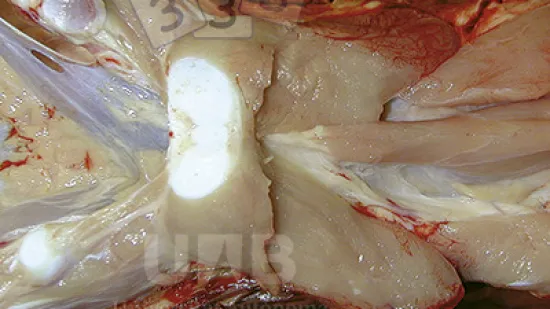

Semaine du 17-Mai-2021

Laquelle de ces bactéries peut produire cette lésion chez les porcelets allaitants ?